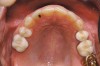

Fig 2 (and Fig 3). Corticotomy SFOT. The patient presented with unesthetic anterior bridgework that was placed at age 14 to compensate for congenitally missing Nos. 7 and 10.

Figure 2

Fig 3 (and Fig 2). Corticotomy SFOT. The patient presented with unesthetic anterior bridgework that was placed at age 14 to compensate for congenitally missing Nos. 7 and 10.

Figure 3

Fig 4. Note gingival inflammation caused by biologic width violation. Provisional restorations were placed on Nos. 6, 8, 9, and 11, and corticotomies were performed from Nos. 3 to 14.

Figure 4

Fig 5. One week postsurgery with mesial buildups on Nos. 5 and 12 and thin pontics on archwire to conceal spaces during closure.

Figure 5